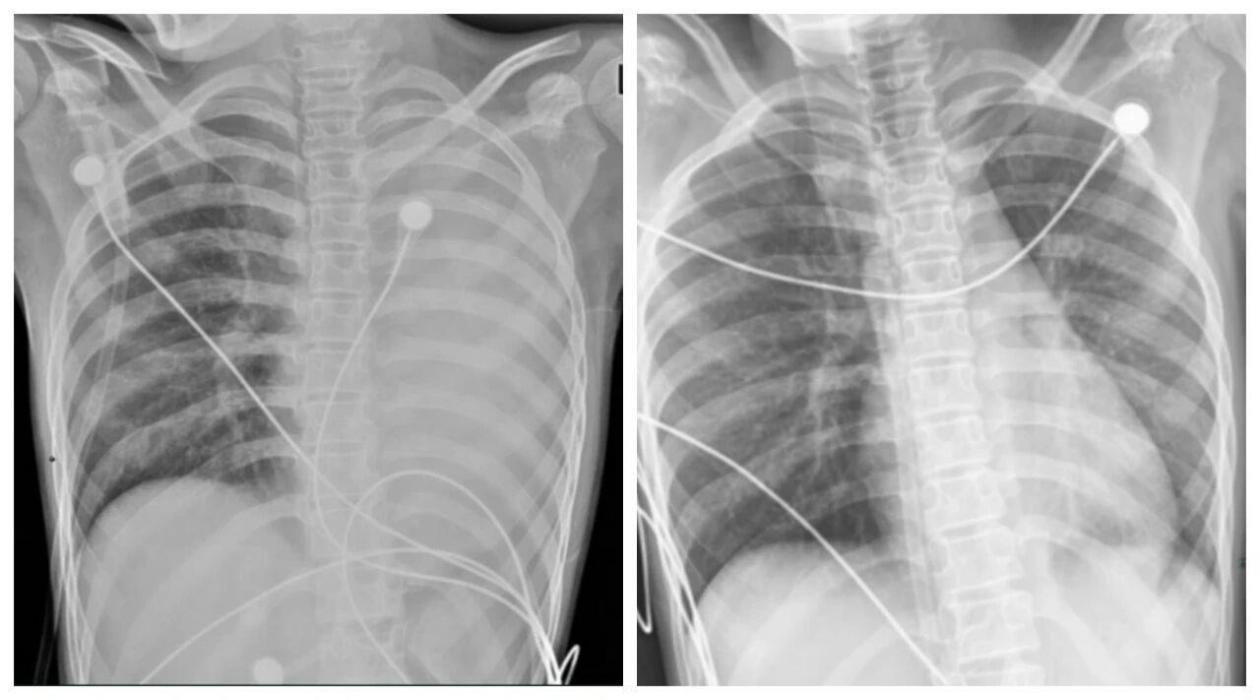

一開始,她只是輕微咳嗽,發熱後在外院檢查提示肺炎、肺不張,轉診到浙大四院兒科時,笑笑出現呼吸急促、胸悶胸痛,血氧飽和度勉強維持在90%左右,胸片顯示左肺已完全呈“白肺”改變,病情急劇惡化。

△笑笑治療前,左肺呈“白肺”狀態,治療後“白肺”被吸收,心臟邊緣清晰可見。圖源:浙大四院

術後第二天,笑笑呼吸困難、胸痛的症狀明顯好轉,病情得到了初步控制。經過精準抗感染、祛痰、抗炎等系列治療,笑笑逐漸康復,順利出院。